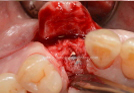

Clinical Cases

• Case1

• Case2

• Case3

• Case4

• Case5

• Case6

• Case7

• Case8

• Case9

• Case10